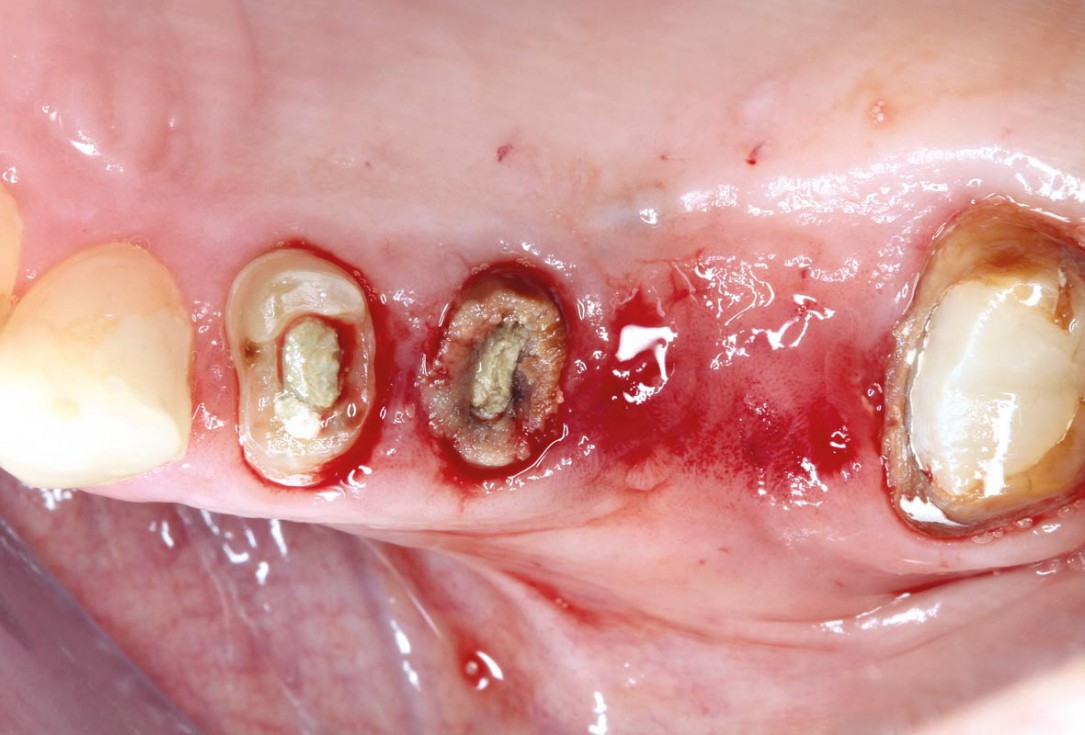

botiss cerabone® & Jason® membrane for GBR - Clinical case by Prof. Dr. Dr. D. Rothamel

Instable bridge situation with abscess formation at tooth #15 after apicoectomy